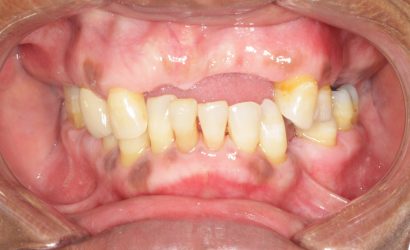

This patient wants implants. We just finished treating her periodontal disease and she is ready for the next phase, however, she has severe bite collapse. In addition, she has uneven ridge in the upper anterior, which would make it challenging esthetically. I asked her dentist to make her a partial denture but the patient kept going back…

You’re right, the bite collapse and the uneven ridge in the upper anterior make things tricky. It’s understandable the patient struggled with the partial denture, especially with the adjustments.

Absolutely, orthodontics is something you should be considering, but it’s not the first step. We need to really figure out where we’re going before… Read more -